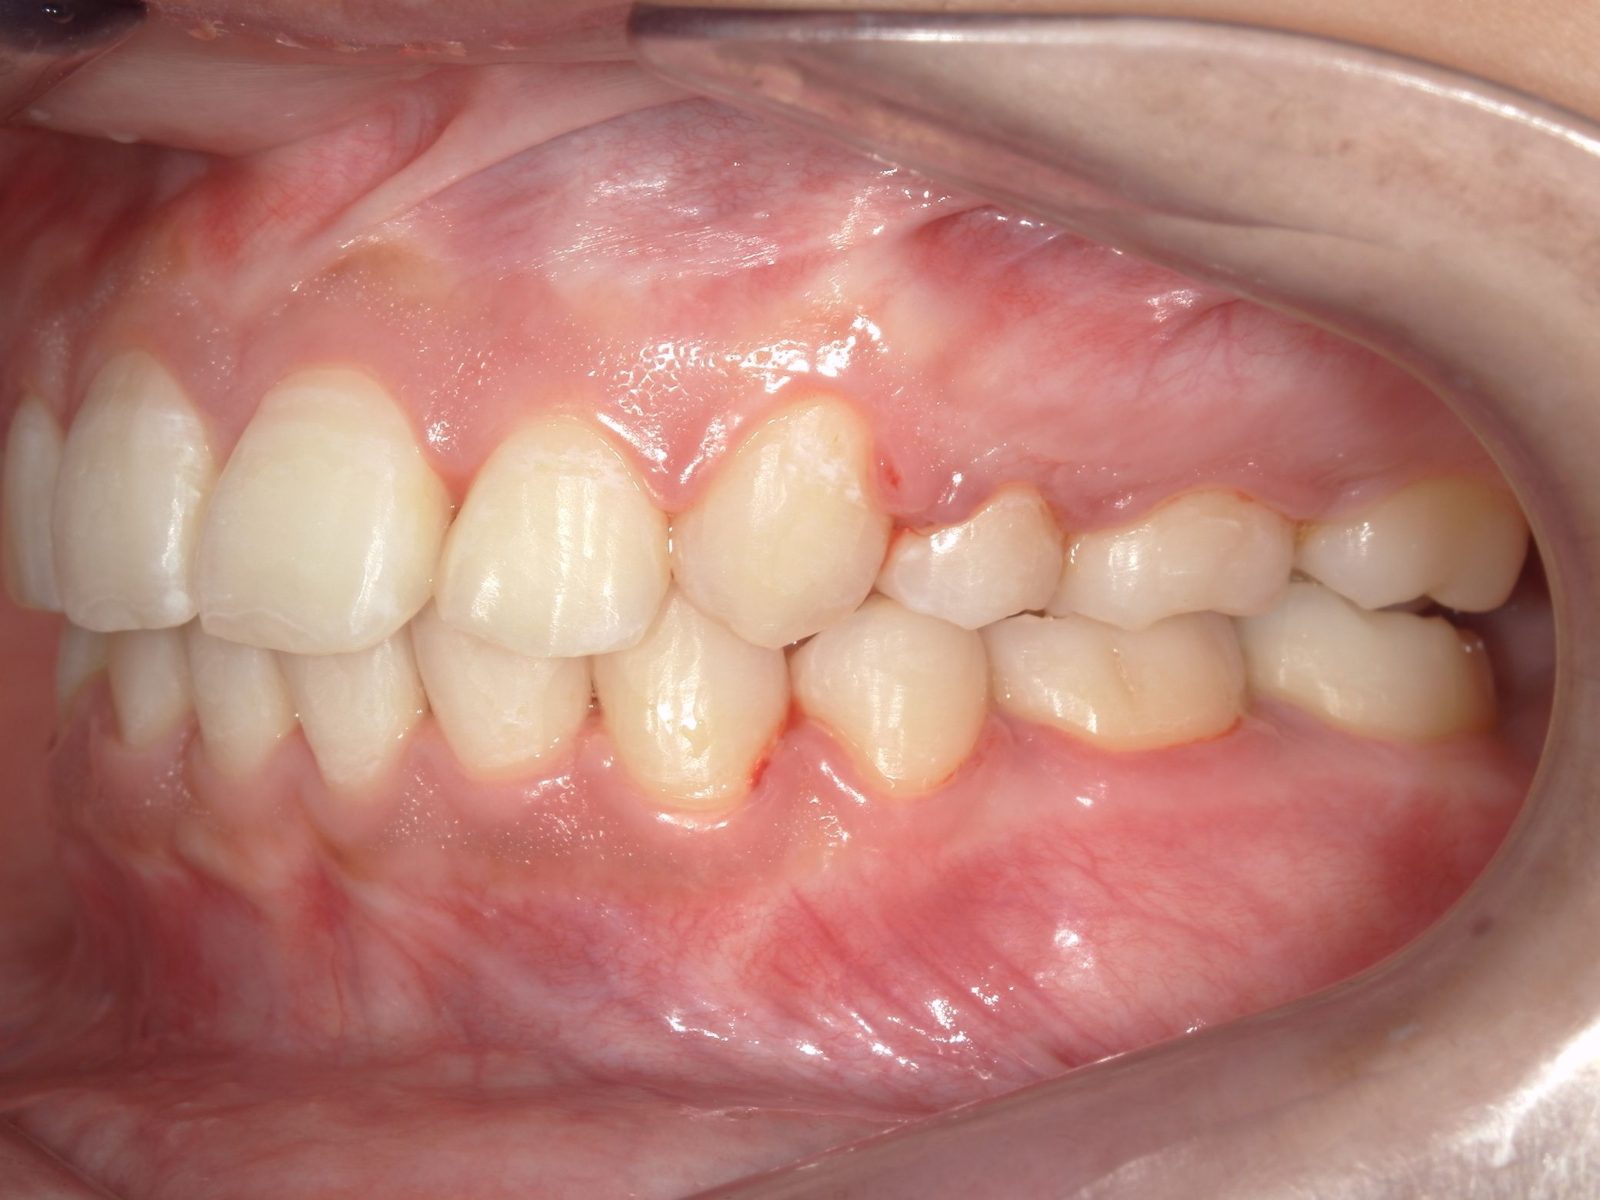

【主訴】出っ歯が気になる

【診断結果】上顎前突

【治療開始時の年齢】18歳

【治療内容】マウスピース型 (カスタムメイド) 矯正装置

【抜歯部位】上下左右4番目

【治療経過】後戻り無

【治療期間】1年8ヶ月

【治療費用】882,200円

【リスク・副作用】

治療初期の段階では痛みや不快感が生じる可能性がある。適切に歯磨きをしないと虫歯になる可能性が高くなる。個人差により予想された治療期間より長くなる場合がある。治療後はリテーナーを装着しないと後戻りしてしまうリスクがある。